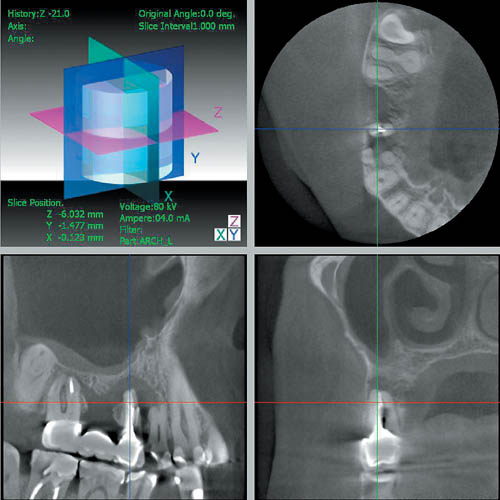

3 DX Accuitomo/FPD после исследования пациента сразу же воспроизводит на экране монитора ИСТИННОЕ трехмерное изображение в трех перпендикулярных друг другу плоскостях.(Рис 2)

Затем возможна реконструкция срезов в вертикальной и горизонтальной плоскости под любым углом к зоне зубочелюстной дуги.

Благодаря этому врач имеет возможность просмотреть изображение более детально (т.е. в трех плоскостях, а также послойно или с необходимым интервалом в режиме видеофильма). Трехмерное изображение 3 DX Accuitomo/FPD открывает новые возможности и перспективы планирования терапевтических, а также хирургических вмешательств в современной стоматологической практике и оториноларингологии (рис. 3).

— позволяет проводить оценку результатов ортопедического и ортодонтического лечения стоматологических пациентов

(рис. 6);